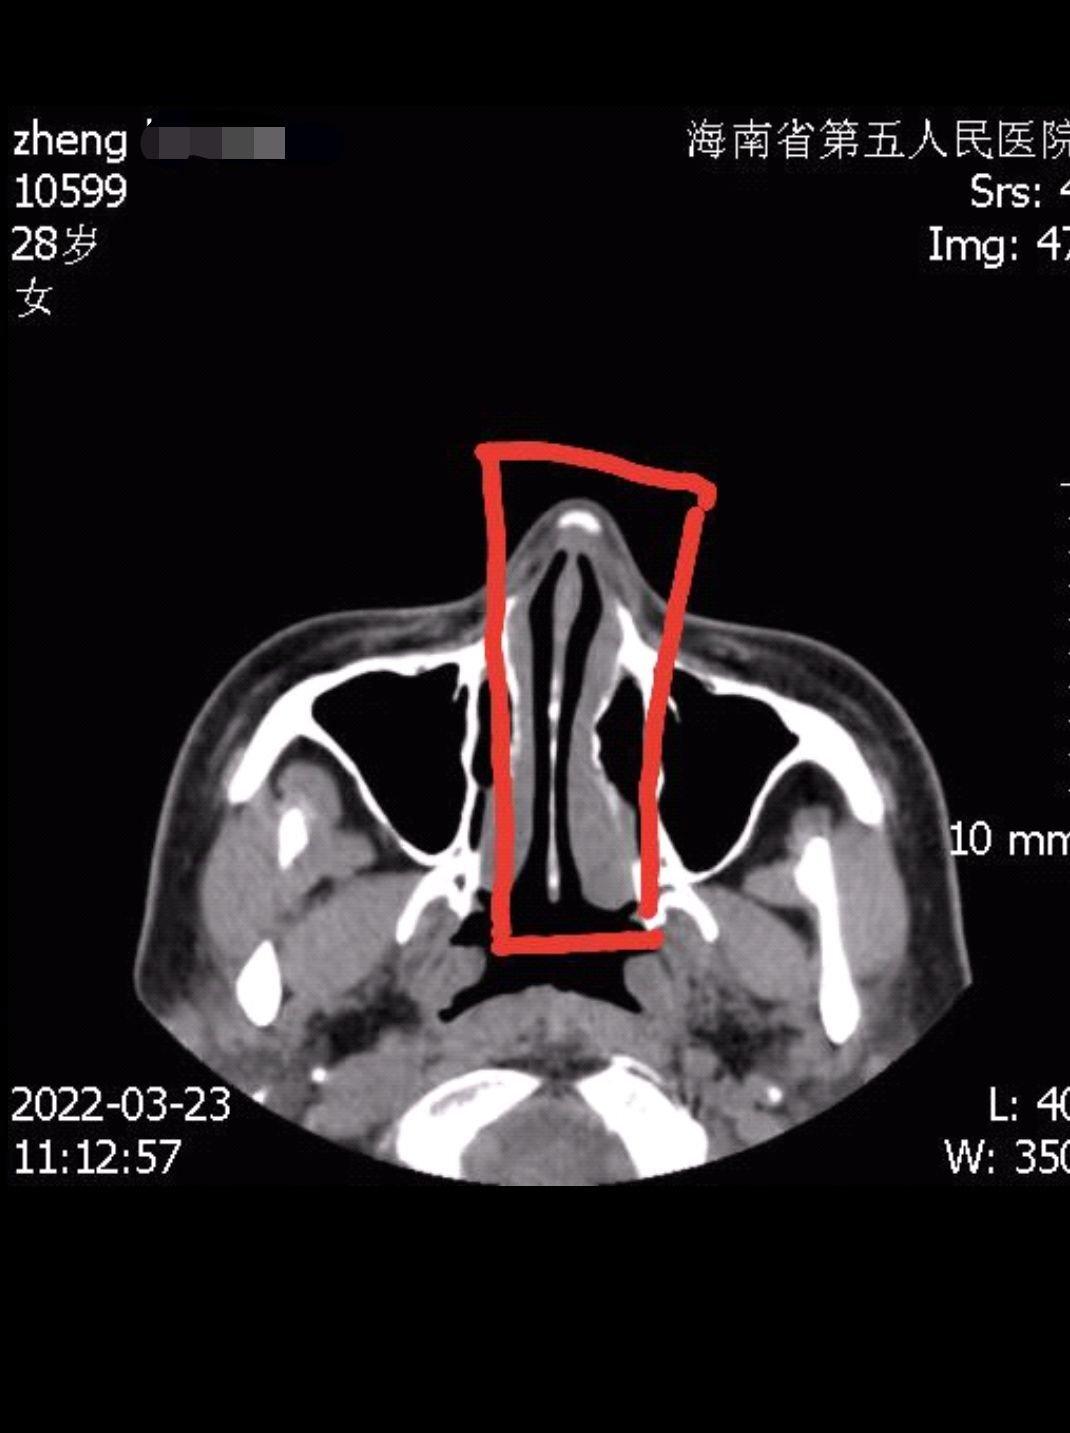

鄭女士在整完后,身邊人提醒她,鼻子怎么變歪了,她對著鏡子細細端詳,感覺鼻子確實被整歪了,為了證實不是眼神和角度問題,她便去海南省第五人民醫(yī)院拍片?!叭说闹饔^視覺可能會看走眼,但機器固定拍攝,騙不了人,片子拍出來后,海南省第五人民醫(yī)院的醫(yī)生明確告訴我,鼻子里面放的假體沒有放正,歪了3毫米左右,所以鼻子是歪的?!编嵟恐钢亲拥腦光片說,這肉眼可見假體是歪斜的,無論是從側(cè)面、正面,還是上面,任何角度都是歪的?!拔椰F(xiàn)在是欲哭無淚,只想趕快湊夠錢,把假體取出來,再也不因為別人制造的面容焦慮而去整形了?!编嵟堪脨赖卣f道。

當(dāng)天,記者實地走訪海南優(yōu)姿妍醫(yī)療美容門診部,現(xiàn)場有數(shù)名醫(yī)美消費者在準備整形,為了不影響該醫(yī)療美容門診部日常運行,記者便在一間辦公室進行采訪。起初,海南優(yōu)姿妍醫(yī)療美容門診部一名主管接受采訪,對方告訴記者,機構(gòu)負責(zé)人因身體問題,不方便出面接受采訪,隨后查看了鄭女士提供的X光片子,表示沒看出假體歪斜。在鄭女士指出歪斜處后,該主管這才承認了歪斜事實。